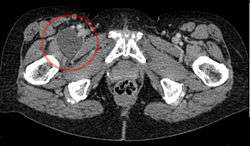

![]() Enlarged iliopectineal bursa in CT - scan | |

The iliopectineal bursa or the iliopsoas bursa is a large synovial bursa that separates the external surface of the hip joint capsule from the normally just the tendon of the iliopsoas muscle.[1]

The most proximal of part the iliopectineal bursa lies on the iliopubic eminence of the superior pubic ramus. The iliopectineal bursa passes across the front of the capsule of the hip joint and extends distally downwards almost as far as to the lesser trochanter.[2]

The iliopectineal bursa frequently communicates by a circular aperture with the cavity of the hip joint.[1]